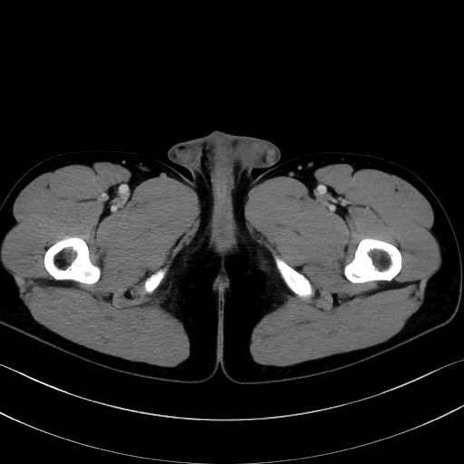

精嚢(seminal vesicle)のCT画像における解剖

症例

【症例】20歳代 男性 スクリーニング